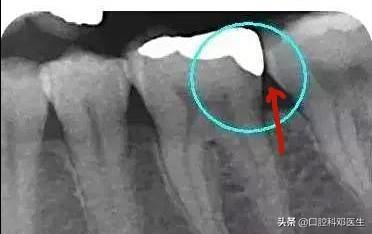

2、邻面洞修复较普通补牙更有优势,能正确的恢复邻面接触点,不易嵌塞食物;

邻面无悬突,接触恢复好